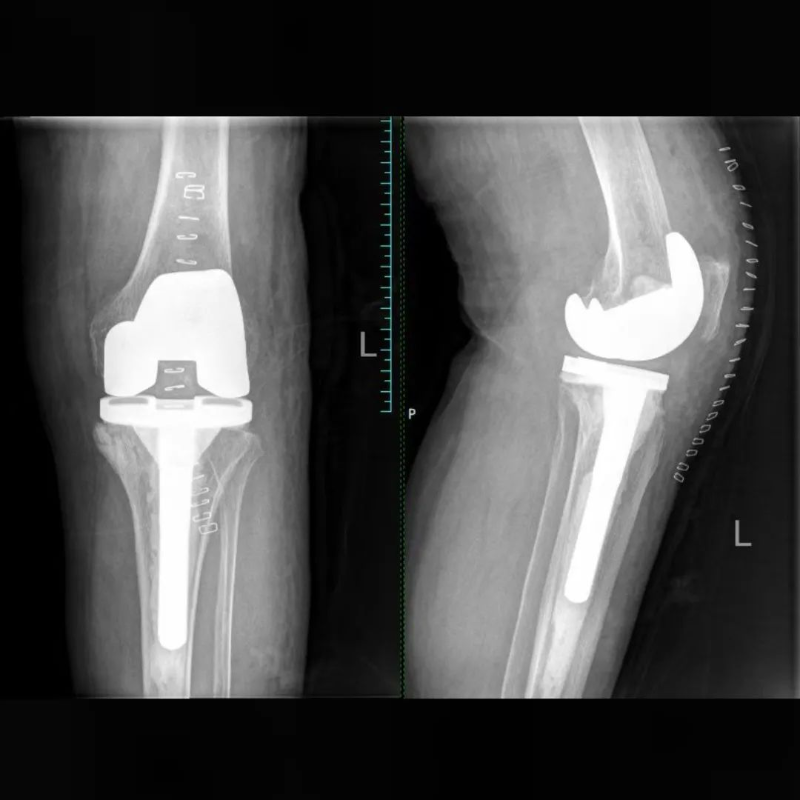

△术后